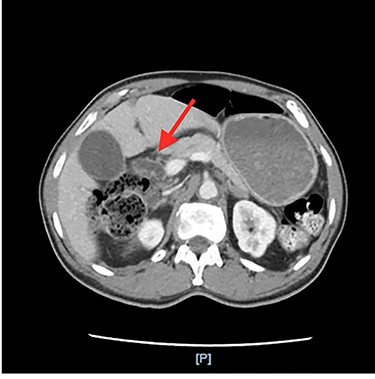

He had an ultrasound (US) and CT abdomen/pelvis showing abnormal intra and extra hepatic biliary ductal dilatation, suspicious for obstruction (Figs. 1 and 2). He then had an MRCP showing ductal dilation with no obvious filling defect. The total bilirubin, direct bilirubin and lipase was normal at 0.4 miligrams per deciliter (mg/dl), 0.1 mg/dl and 38 units per liter (unit/L), respectively. Liver function tests were within normal limits.

Annular pancreas encircling the pylorus and the first and section portions of the duodenum.